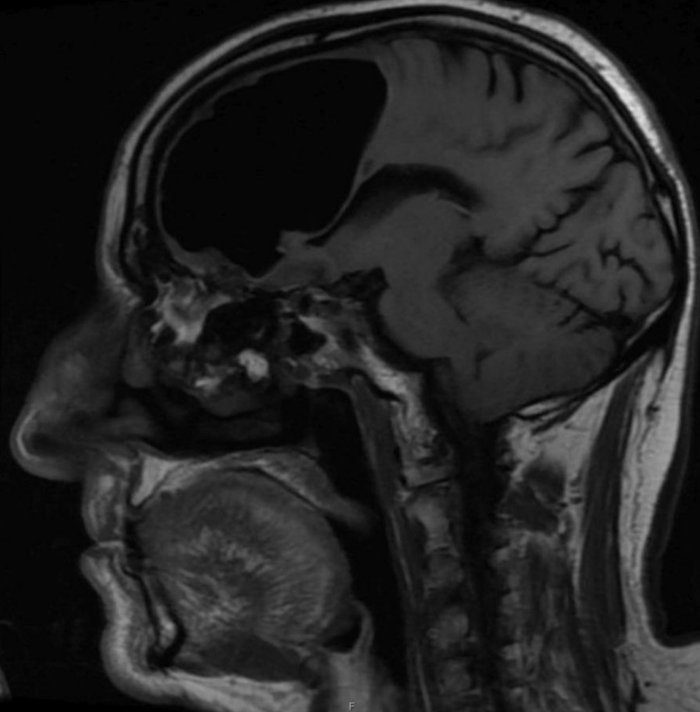

بر اساس گزارش ساینس الرت، تصاویر سیتیاسکن مغز این بیمار نشان داد، بخش بزرگی از لوب پیشانی راست مغز مرد ناپدید شده است.

نتیجه سیتیاسکن گیجکننده بود، حفرهای بزرگ و سیاه به وسعت 9 سانتیمتر در لوب پیشانی سمت راست مرد دیده میشد. در مرحله بعدی مغز مرد با دستگاه MRI مورد بررسی قرار گرفت و پزشکان دریافتند ماده مغزی در جمجمه بیمار ناپدید نشدهاست، بلکه درون جمجمهاش حفرهای از هوا به نام پنوماتوکوئل ایجاد شدهبود که معمولا در بیمارانی دیده میشود که دچار آسیبدیدگی صورت یا عفونت تنفسی شدهاند یا در جمجمه آنها جراحی انجام شده است.

اما هیچیک از این عوامل در این بیمار به ایجاد این پنوماتوکوئل بزرگ منجر نشده بود. پزشکان همچنین در استخوان اتموئید مغز مرد،استخوانی که حفره تنفسی را از مغز جدا میکند، نوعی تومور خوشخیم پیدا کردند. این بخش آسیبدیده استخوانی باعث شده بود تا هوا به درون جمجمه نشت کرده و پدیده ای به نام تاثیر لوله یکطرفه ایجاد کند.